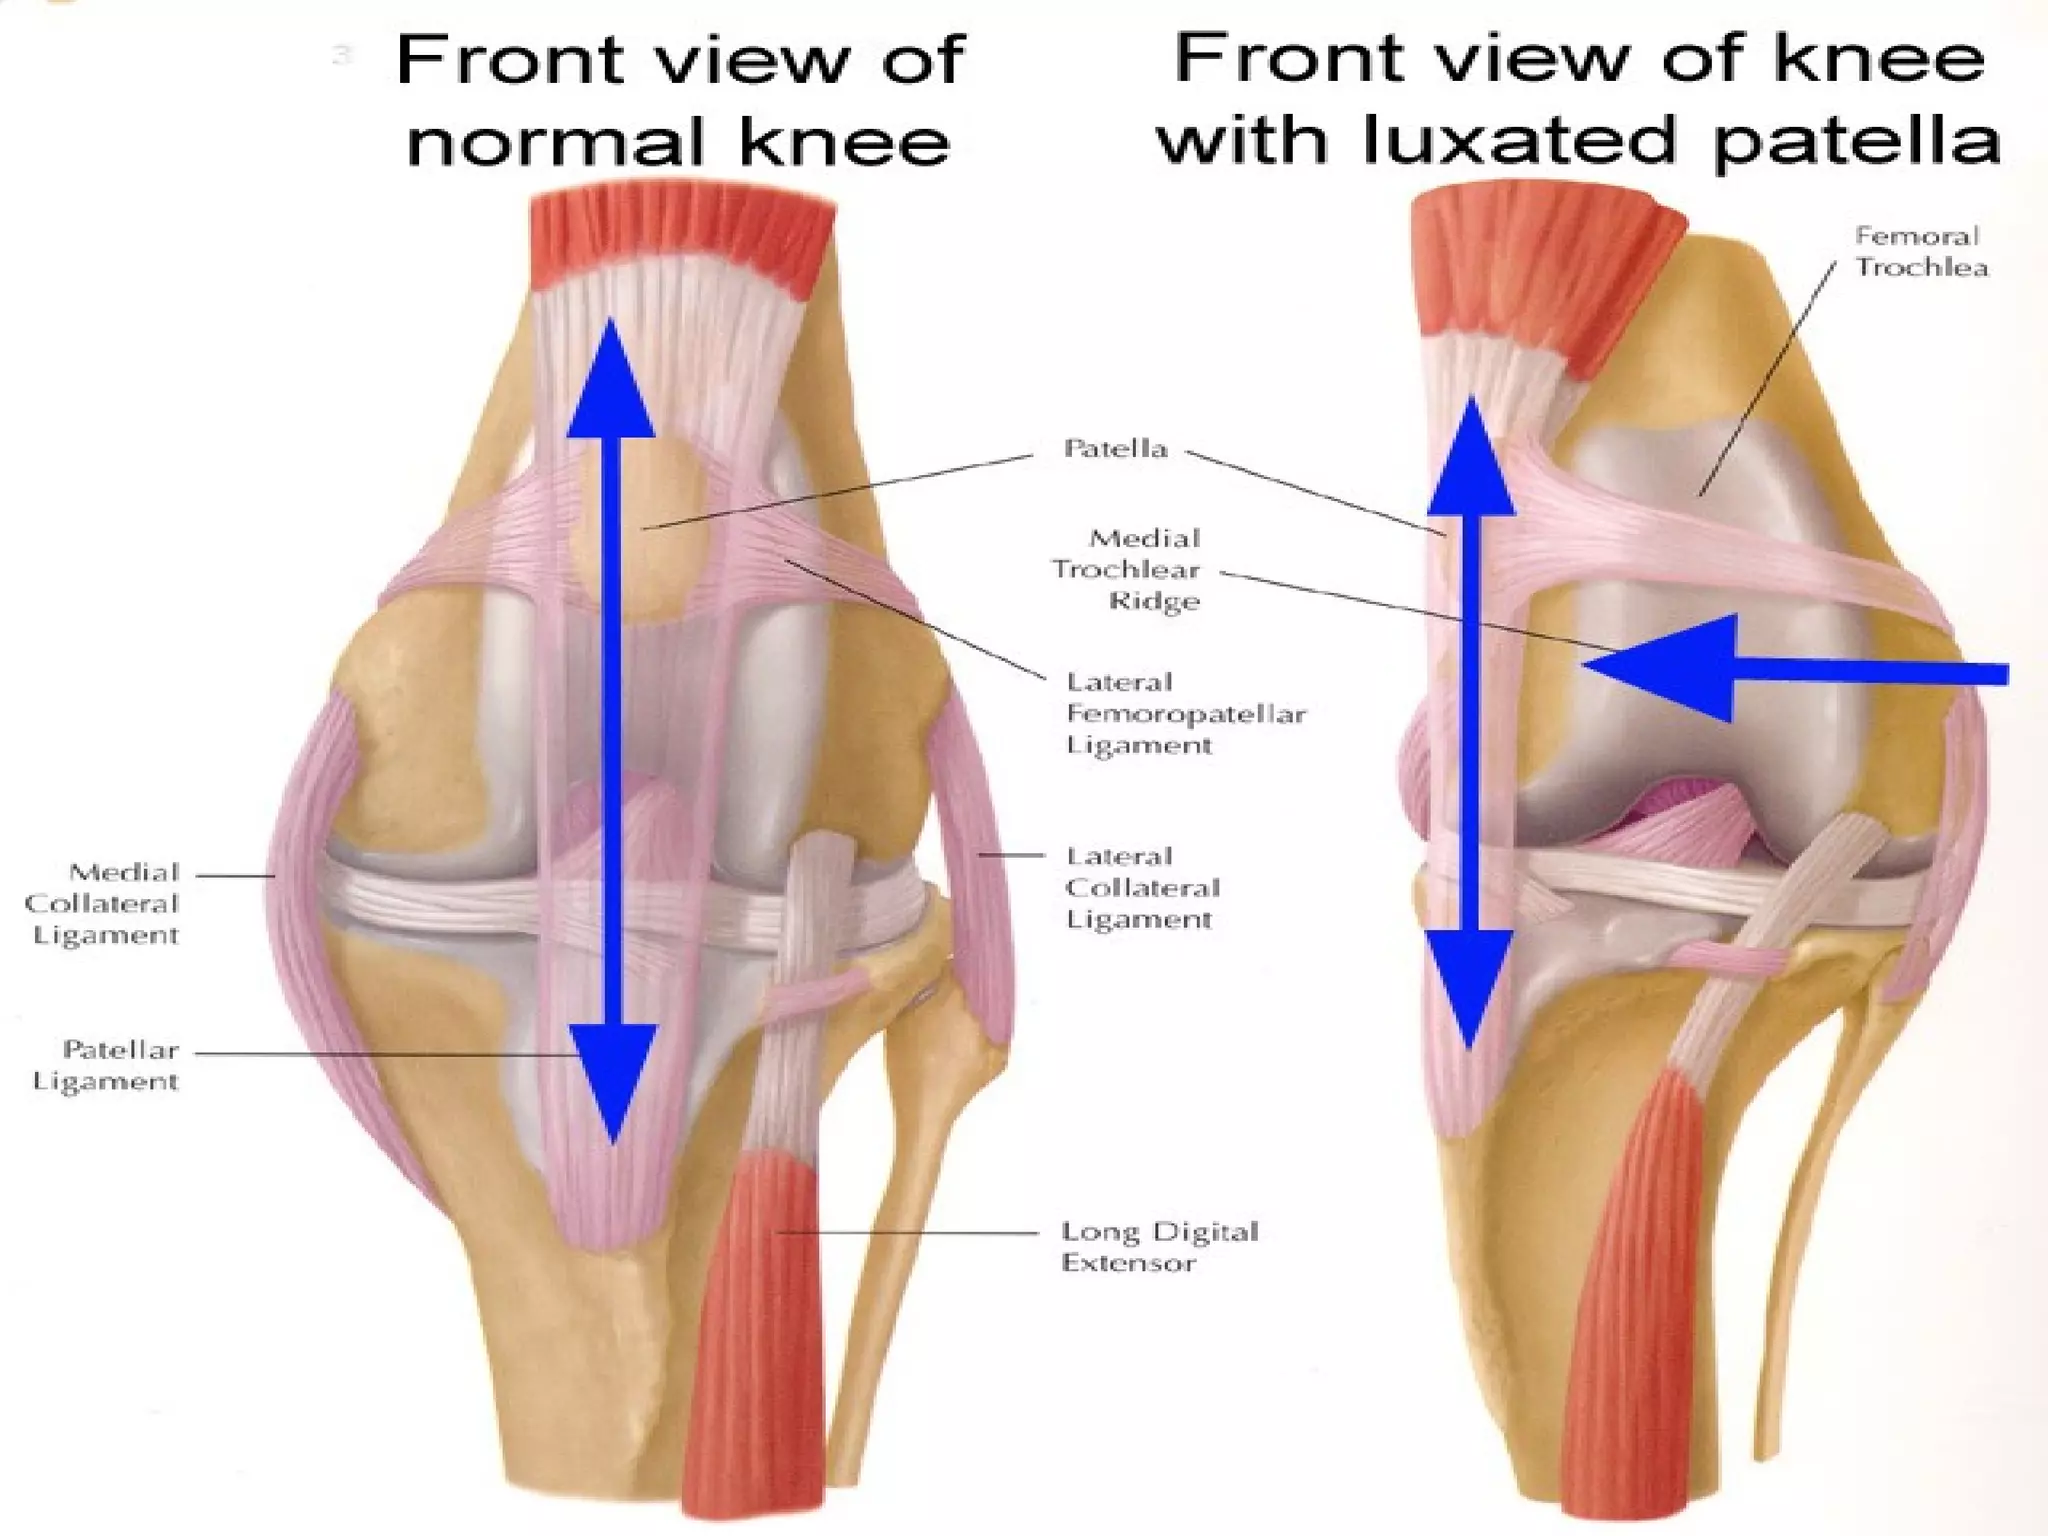

There are three types of patella dislocation: acute, recurrent, and habitual. Acute dislocation occurs suddenly due to quadriceps contraction with the knee flexed and results in the patella dislocating laterally, causing pain, swelling, and inability to straighten the knee. Recurrent dislocations are caused by ligament laxity or anatomical abnormalities and damage bones with repeated dislocations. Habitual dislocations occur every time the knee is flexed and present in early childhood.